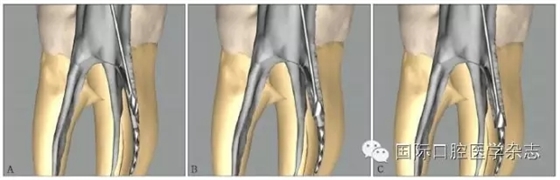

3.2.4 器械材質(zhì)類(lèi)型的評(píng)估 不銹鋼K銼取出的概率略高于鎳鈦機(jī)用器械,這或許是因2類(lèi)器械的錐度、橫截面設(shè)計(jì)和使用方法的截然不同所致。機(jī)用器械多為大錐度,在其旋轉(zhuǎn)運(yùn)動(dòng)時(shí),器械尖端更易鎖入根管壁。一般情況下,分離的鎳鈦器械較不銹鋼器械更難從根管中取出[14],原因包括以下幾點(diǎn):1)鎳鈦器械為旋轉(zhuǎn)運(yùn)動(dòng),更傾向于嵌入根管壁內(nèi)而難以取出[3];2)尤其在使用超聲的情況下,鎳鈦器械因溫度升高容易發(fā)生二次分離[15];3)由于鎳鈦器械有良好的可彎曲性能,分離于彎曲根管中的鎳鈦器械往往抵在根管的外側(cè)壁上而不是保留在根管的中心,增加了取出的難度[16](圖7);4)一般分離器械越長(zhǎng),越容易取出,因?yàn)檩^長(zhǎng)的分離器械往往位于根管的更冠方部位,而分離的鎳鈦器械往往較小[17]。

圖 7 分離于彎曲根管的鎳鈦器械往往抵在根管外側(cè)壁,而不會(huì)保留在根管的中心

3.2.5 取出難度評(píng)估 多數(shù)情況下,如果分離器械上1/3能夠暴露,通常能夠取出。位于直根管、近根管口的分離器械較位于彎曲根管的器械容易取出。位于根管通暢部分的分離器械通常可以取出。如果分離器械位于根管彎曲附近,并且牙本質(zhì)厚度容許建立從根管口到器械冠方的通道以接近其冠部末端,而不至于產(chǎn)生穿孔等并發(fā)癥,則仍有可能將其取出。在這些病例中,都必須建立到達(dá)分離器械上部的直線(xiàn)通路。如果器械分離于彎曲根管的根尖部,則很難建立安全的通道,且分離器械移動(dòng)可能造成器械超出根尖孔,風(fēng)險(xiǎn)較大,通常不太可能將其去除(圖8)。

A:分離器械位于較直的根管中上部分,較容易取出;B~D:分離器械位于根管彎曲之下或彎曲根管近根尖部,無(wú)法取出。

圖 8 取出難度的評(píng)估